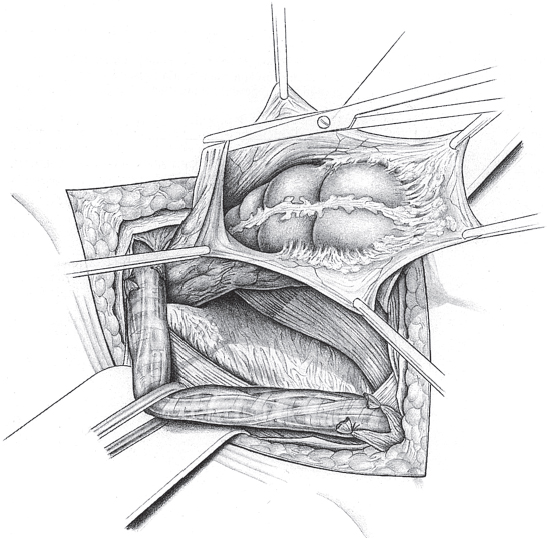

When the hernia is indirect, the sac is treated and the femoral compartment is then explored digitally through the expanded deep inguinal ring (

Fig. 3.1).

Sutured repair, e.g., by the Shouldice method (see section

2.2.2.4), can then be carried out, especially in younger patients. Unlike in men, the deep inguinal ring is closed completely. The proximal stump of the round ligament can be included in the lateral part of the Shouldice suture (

Fig. 3.2).